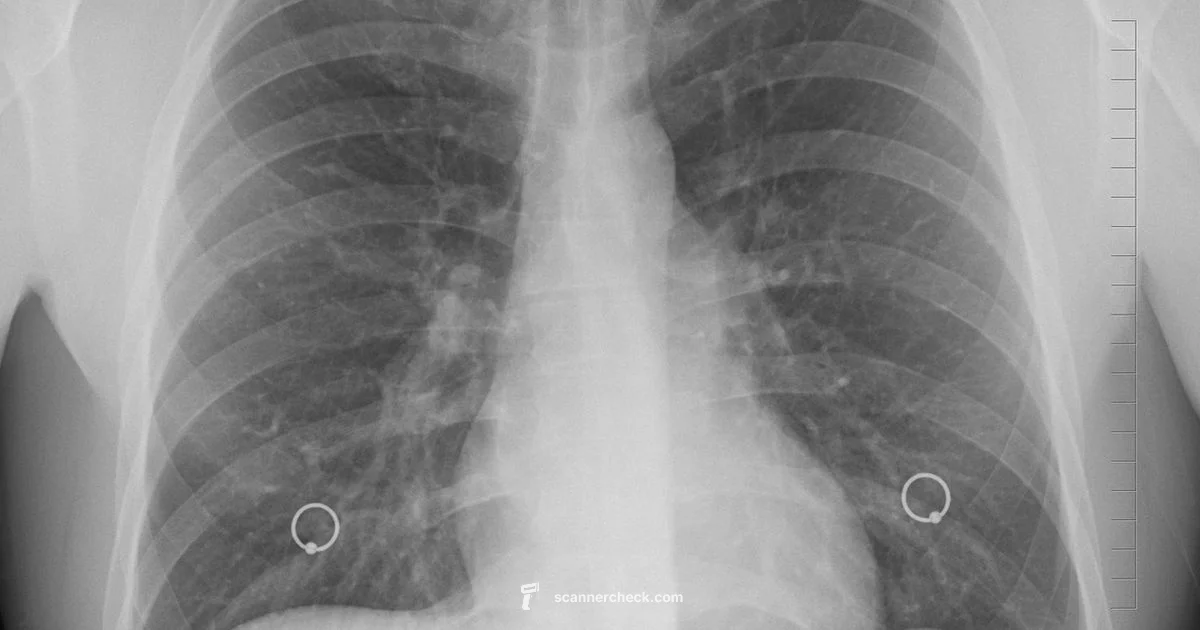

The phrase 'is scan the same as x ray' often appears in patient FAQs, but it obscures important distinctions between imaging technologies. In medical imaging, 'scan' is a broad term that can refer to any modality that creates an image of the inside of the body, including X-ray radiography, CT, MRI, and ultrasound. By contrast, an X-ray is a specific technique that uses ionizing radiation to produce a two-dimensional projection image of structures such as bones, lungs, and teeth. Understanding the nuance helps clinicians order and interpret studies appropriately. According to Scanner Check, the practical takeaway is that X-ray imaging is fast, affordable, and widely accessible, making it the go-to first step in many triage situations, while other scanning modalities offer deeper tissue contrast or three-dimensional information.

This initial distinction matters in everyday practice: in emergency departments, a quick X-ray can rule out fractures or major chest injuries, while CT may be reserved for more complex trauma or detailed anatomical assessment. For dental work, panoramic X-rays provide broad overviews, whereas cone-beam CT offers high-resolution detail for implanted devices. The choice should balance diagnostic yield, patient safety, and resource availability. Scanner Check Analysis, 2026, reinforces that modality selection is a clinical decision, not a fixed preference, and that understanding each method’s limitations is essential for accurate interpretation and appropriate follow-up.

X-ray radiography remains the most accessible and fastest imaging modality in many healthcare settings. It produces a flat, two-dimensional image by passing ionizing radiation through the body onto a detector. CT (computed tomography) uses multiple X-ray cross-sections collected from different angles to build a detailed three-dimensional model, offering superior anatomic detail and the ability to reconstruct views in various planes. MRI (magnetic resonance imaging) relies on strong magnetic fields and radiofrequency pulses to generate high-contrast images of soft tissues, without ionizing radiation, though it is typically more time-consuming and resource-intensive. Ultrasound uses high-frequency sound waves to visualize real-time movement and blood flow, excelling in soft tissue assessment, obstetrics, and certain vascular studies. Each modality has scenarios where it excels and others where it is less informative. A clear understanding of these differences helps clinicians select the most appropriate tool for a given clinical question.

In an acute trauma setting, a chest X-ray can quickly identify pneumothorax or rib fractures, guiding immediate management. For suspected pulmonary embolism or complex skull trauma, a CT or MRI may be warranted to obtain detailed, cross-sectional information. In pediatric dentistry, specific X-ray views reveal alignment and development, while more advanced 3D imaging is reserved for surgical planning. In obstetrics, ultrasound or MRI are often preferred over radiographs when evaluating fetal or placental conditions. Across these scenarios, the central principle remains: tailor imaging to the clinical question, minimize risk, and ensure results meaningfully inform care.